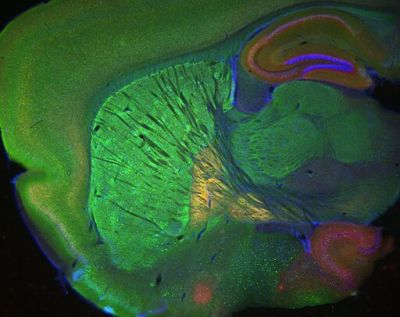

Sagittal mouse cannabinoid receptor nuclei – histology slide

Sagittal section of an Nr4a1-eGFP transgenic mouse stained for the CB1 cannabinoid receptor and DAPI to show nuclei. Image was taken with a Zeiss Lumar stereomicroscope.